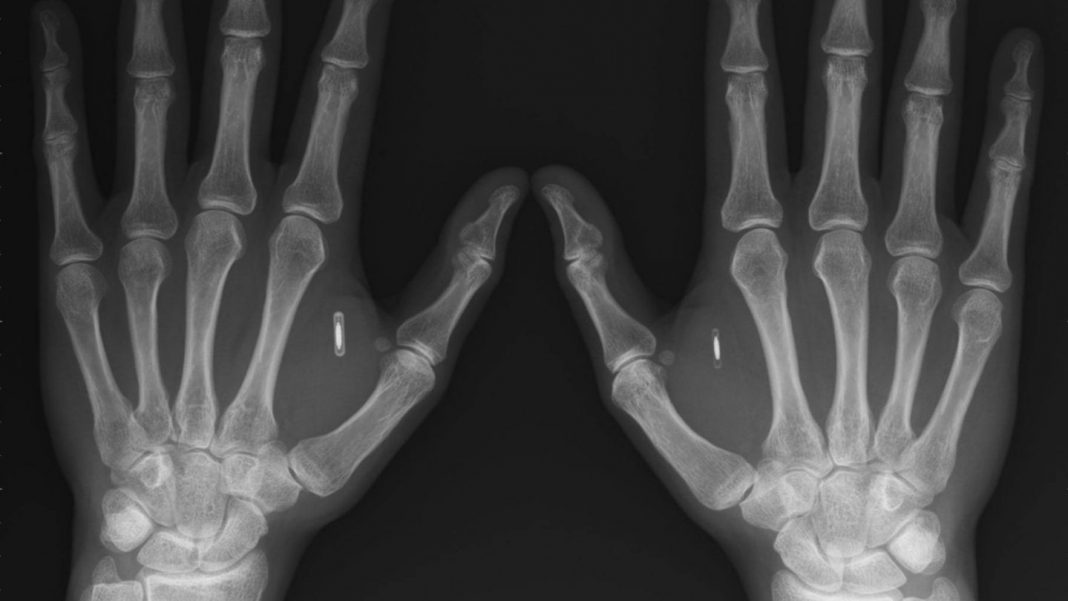

“El implante debe estar dentro del campo electromagnético de un lector RFID [o NFC] compatible. Solo cuando hay un acoplamiento magnético entre el lector y el transpondedor, el implante puede ser leído”, afirmó Patrick Paumen, quien es una de las primeras personas en colocarse un microchip. Sin embargo, uno de los principales interrogantes que surgen con su empleo, es que sucederá cuando estos comiencen ser cada vez más avanzados y se llenen de datos personales, que puedan ser robados y/o alterados.